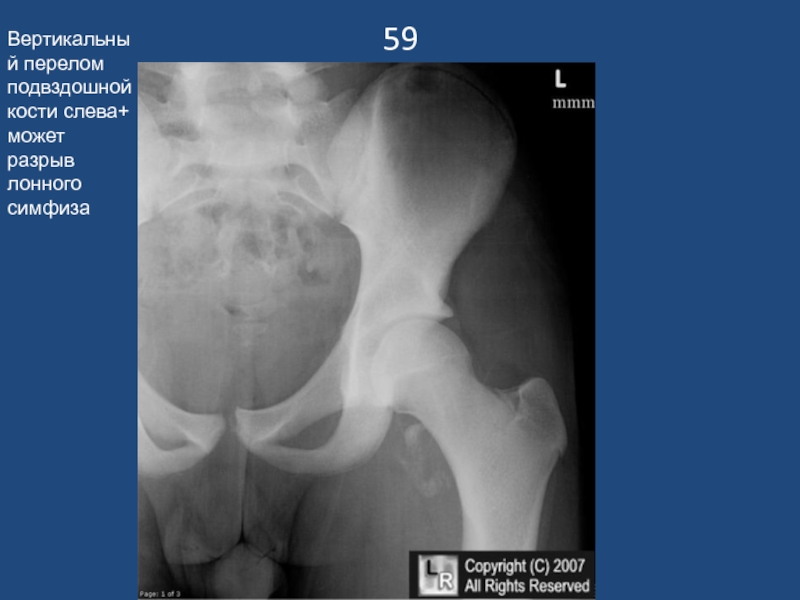

Слайд 6059

Вертикальный перелом подвздошной кости слева+ может разрыв лонного симфиза

59Вертикальный перелом подвздошной кости слева+ может разрыв лонного симфиза